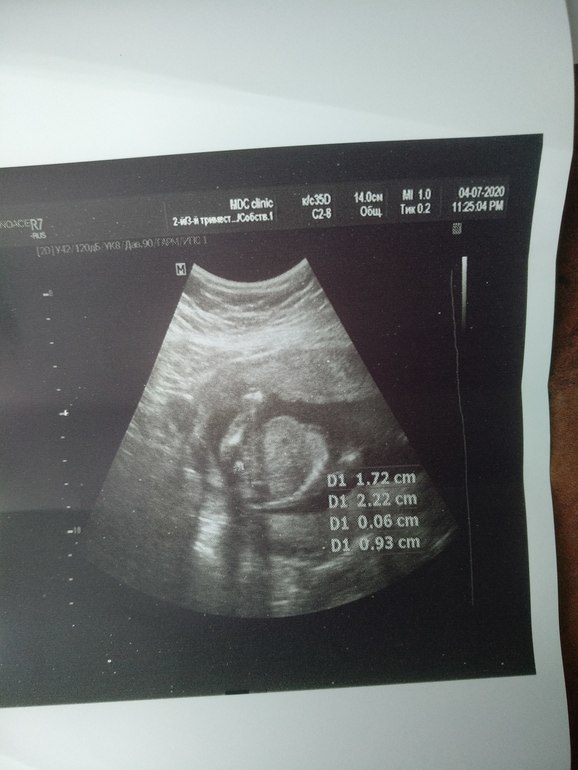

Я бы по третьему фото тоже бы сказала, что мальчик, но раз нипт показал, девочка, то тогда я в ущи ничего не понимаю. А когда вам на скрининг следующий?

На 2 и 3 фото точно мальчика разглядела!

Врачь сказала мальчик , но я что то ни одного фото не увидела где точно мальчик , и не верится мне , мне кажется она ошиблась , результат НИИП уже жду месяц, мой гинеколог ушла в отпуск , вот скоро второй скрининг еще там спрошу, просто хотела что б вы все посмотрели, не одна я ничего не вижу , хотя доктор говорит я вам везде плюсики поставлю где смотреть , ну что то беленькое и все , вот что я вижу.

Где плюсик стоит, там видно «кофейное зернышко» -это на девочку указывает... мне вот на втором скрининге Доктор сказал «девочка», хотя я нипт делала, и уже в 11 недель знала, что будет здоровый мальчик))) Желаю вам мальчика, А главное ,пусть пусть будет здоровый малыш!!!